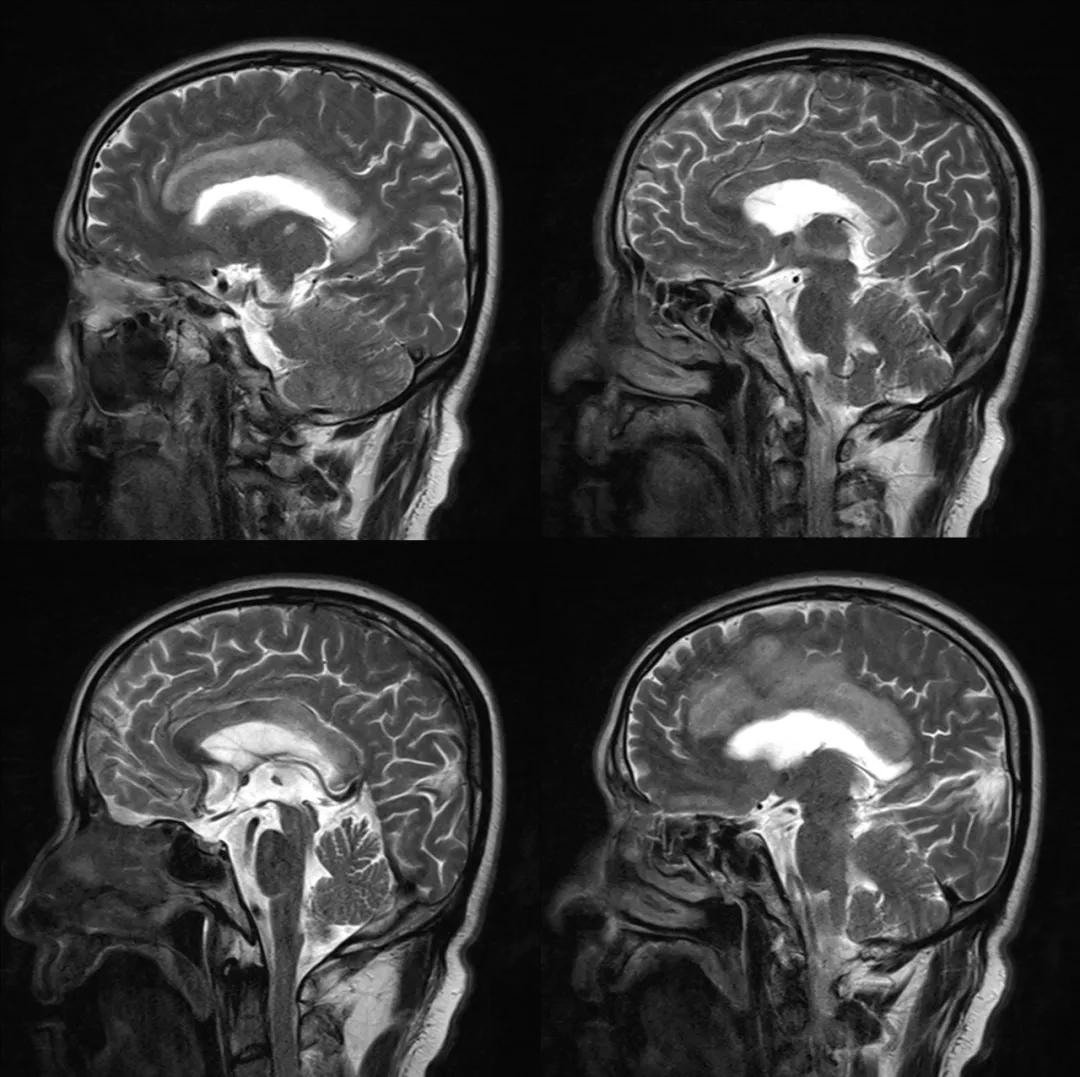

- 急性期表现为胼胝体弥漫性肿胀,T1WI呈稍低信号,T2WI及FLAIR呈稍高信号,以矢状位观察最佳,可单独累及胼胝体压部或整个胼胝体,DWI呈高信号,ADC图呈低信号,部分患者可观察到脑室周围白质或内囊受累,少见皮层受累,表现为扩散受限,不强化和强化病例均可见到。如果增强扫描可见胼胝体有不同程度强化,呈小灶状或不规则斑片状,系血脑屏障破坏所致(如本例),本例患者处于急性期。

原发性胼胝体变性急性期:T2WI矢状位(A)清晰观察到弥漫胼胝体病变,FLAIR呈高信号(B),DWI呈高信号(C),ADC图呈低信号。

上排:原发性胼胝体变性急性期

下排:原发性胼胝体变性慢性期,表现为胼胝体萎缩、软化

急性期原发性胼胝体变性(胼胝体压部及体部病变,CT呈低密度,T1WI呈稍低信号,FLAIR呈稍高信号,扩散受限)向慢性期转变,慢性期胼胝体压部病灶出现坏死或囊变,FLAIR呈低信号